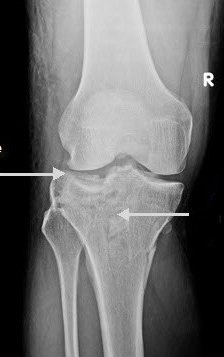

These fractures can be quite subtle and should always be considered when assessing acute knee injuries. Usually the common patterns of tibial plateau fractures are identified on plain films (AP, LAT, OBLIQUES).

Some subtle injuries where the bone is marginally impacted are only identified on CT or MRI.